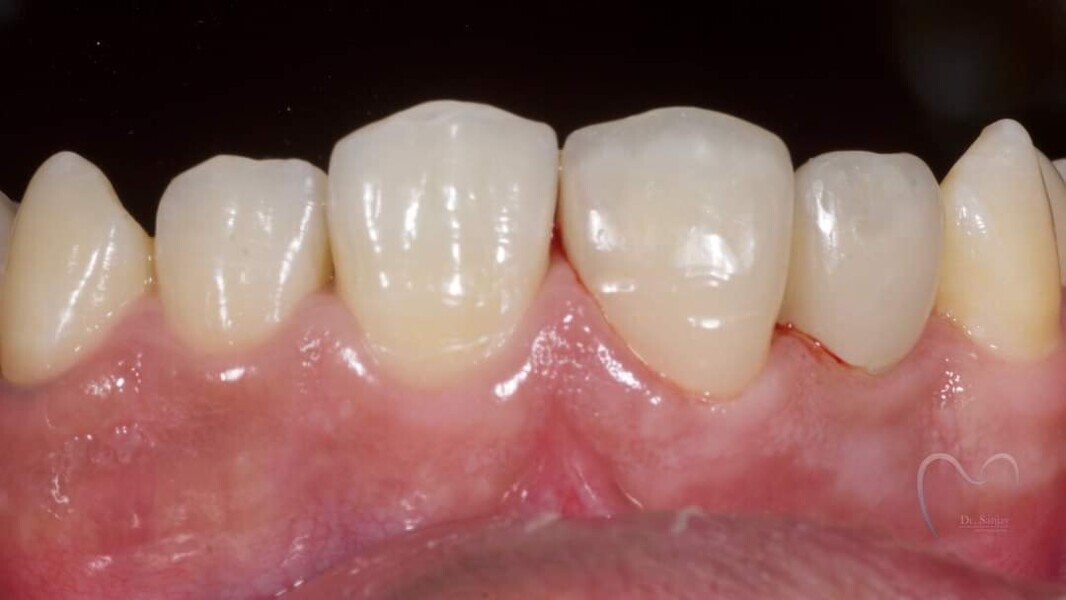

Esthetic Rehabilitation of Maxillary Anterior Teeth: Dr Sanjay Sah